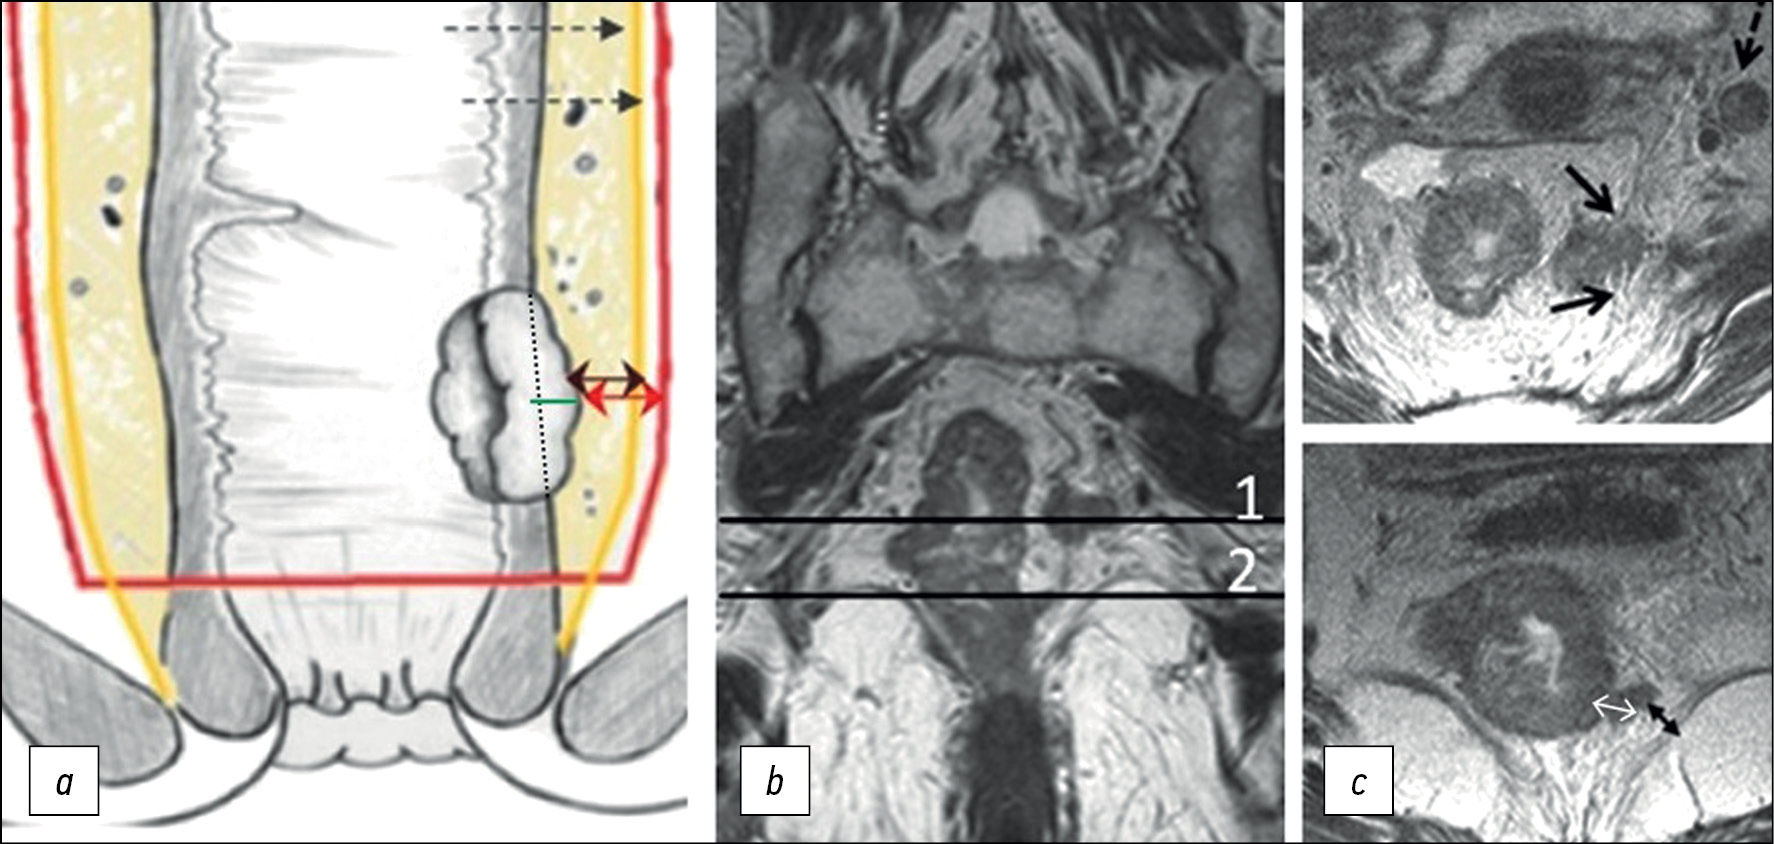

The depth of extramural invasion is the maximum distance from the outer edge of the muscular layer of the wall at the base of the extramural component of the primary tumor to its outer edge, as observed on high-resolution T2-WI oriented perpendicular to the intestinal wall at the level of the tumor (Fig. 2). The depth of extramural invasion is used to determine the substage of T3 tumors.

Fig. 2. Circular border (edge) of rectal resection during total mesorectumectomy. (a) Diagram showing extramural growth of the tumor (green line); mesorectal fascia (yellow line); circular border (edge) of resection (red line); distance from the tumor to the mesorectal fascia (double black arrow); distance from the tumor to the circular border (edge) of resection (double red arrow). (b) T2-weighted images in the coronal plane of the tumor of the lower ampullary part of the rectum with extramural vascular invasion and deposit at the level of axial T2-weighted images. (c) Upper axial section corresponds to the level of the deposit involving the mesorectal fascia (black arrows), extramesorectal lymph node (dotted arrow). The lower axial section corresponds to the level of extramural vascular invasion. The depth of extramural invasion (a double white arrow). The distance from the tumor to the elevator muscle of anus (a double black arrow).

Circumferential resection margin (CRM) is a surgery and pathology term defined as the surface of surgical excision of the non-peritoneal part of the rectum, which should pass along the mesorectal fascia when performing a total mesorectumectomy.

The status of CRM is determined by histological examination of the surgically removed rectum specimens. It can be predicted based on MRI by the shortest distance between the extramural component of the tumor/deposit/affected lymph node and the mesorectal fascia. Involvement of the CRM is indicated as CRM(+) if this distance is ≤1 mm. For low-lying rectal cancer, the shortest distance is determined to the elevator muscle of anus. The distance from enlarged lymph nodes without signs of extracapsular spread (with smooth contours) is not considered and should be regarded as CRM(−) [13].

Extramural vascular/venous invasion in histological examination represents intravascular growth of the tumor beyond the rectal wall, serving as a predictor of poor prognosis, lymphatic and distant metastases, and tumor recurrence [14–17]. On T2-WI, extramural vascular/venous invasion is characterized by the spread of a tumor signal into the vascular structures of the mesorectal tissue [6, 18, 19], which can be combined with the increased diameter of the affected vessel or with the tumor extending beyond its walls with the formation of a node, beaded, or worm-like structure. It is important to note that the MRI assessment of extramural venous invasion in vessels less than 3 mm in diameter is unreliable. When determining the category “T” (T3 and T4 tumors) in cases of fusion of the primary tumor and an extramural venous invasion lesion, their total size should be considered.